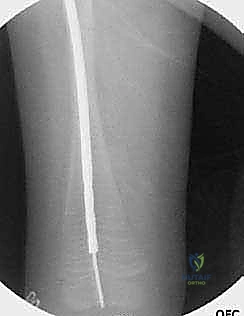

تُعد هذه العملية من أدق العمليات في جراحة عظام الأطفال، وتتطلب مهارة استثنائية كما هو الحال مع البروفيسور محمد هطيف. يتكون المسمار التلسكوبي (Fassier-Duval) من جزأين يتداخلان ببعضهما البعض (مثل التلسكوب). يتم تثبيت أحد الأطراف في أعلى العظم والطرف الآخر في أسفله. عندما ينمو العظم، ينزلق الجزء الداخلي من المسمار للخارج، مما يسمح للعظم بالنمو الطبيعي دون أن ينثني أو ينكسر.

بعد تقويم العظم وجعله مستقيماً كحبات المسبحة على خيط، يتم إدخال السلك الدليلي (Guide Wire). ثم يتم إدخال الجزء الخارجي (الأنثوي) من المسمار التلسكوبي وتثبيته في الجزء العلوي من العظم (Epiphysis).

بعد ذلك، يتم إدخال الجزء الداخلي (الذكري) من المسمار عبر الجزء السفلي من العظم وتثبيته في المشاشة السفلية. هذا التصميم العبقري يضمن حماية العظم بالكامل من الداخل.

المسمار العادي ذو طول ثابت، وعندما ينمو عظم الطفل، يصبح المسمار قصيراً ولا يحمي الأطراف الجديدة للعظم، مما يؤدي لكسرها. أما المسمار التلسكوبي فهو مصمم من قطعتين تتمددان مع نمو العظم (مثل هوائي الراديو القديم)، مما يوفر حماية دائمة للعظم طوال فترة النمو.